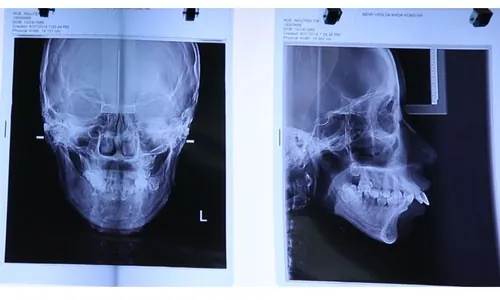

Nguyễn Thị Huê được thăm khám chuyên sâu, chụp xương cùng máy CT SCanner, bác sĩ chuyên khoa chỉnh hình hàm mặt nhận định đây là trường hợp KHÓ, PHỨC TẠP.

Thông qua hình ảnh chụp xương hàm mặt, bác sĩ có thể khẳng định phần tiền hàm trên hình thành quá phát, đẩy ra ngoài tới 3cm.

Do vậy, khớp cắn hai hàm lệch hoàn toàn ảnh hưởng trực tiếp tới sự cân đối khuôn mặt và chức năng ăn nhai của bạn Nguyễn Thị Huê.

Huê chụp xương bằng công nghệ 4.0 đánh giá tình trạng mức độ khuyết điểm hàm và răng